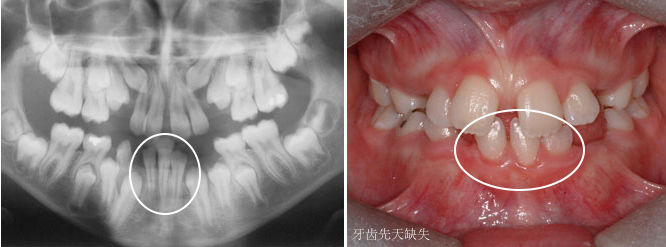

如果牙齿比平均该长牙的年龄,晚了12个月还没有长牙的话,叫做牙齿迟萌。造成牙齿迟萌的原因有很多,比如,多生牙、牙瘤、囊肿会导致牙齿迟萌。

如果你家孩子比平均该长牙的年龄,晚了12个月还不长牙,你需要及时带孩子看牙医了。牙医一般会拍牙片来看看牙床内是否有未萌出的牙齿。

最为常见的是上颌切牙的迟萌。乳切牙因为外伤、蛀牙等原因,造成了过早脱落,致使牙龈反复摩擦增厚,导致下面的恒牙萌出困难,此时需要去进行牙齿助萌。

上颌切牙迟萌